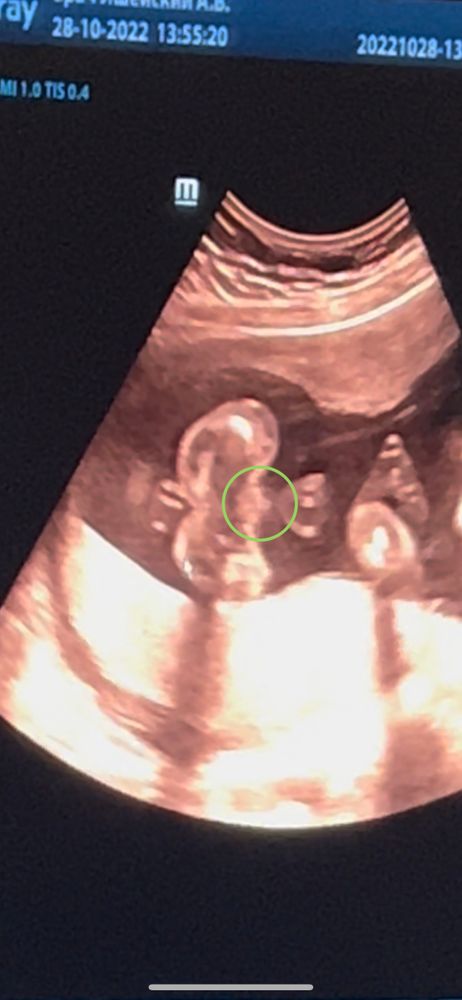

На фото зелеными стрелками отмечены половые органы.